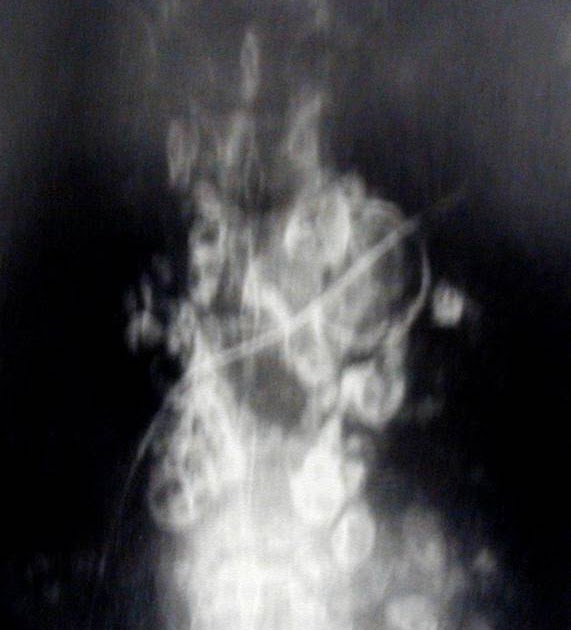

Plain abdominal radiograph revealed multiple eggshell calcifications What Is Egg Shell Calcification eggshell or rim calcifications. according to fraser and pare, “eggshell calcification is uncommon; It consists of a ring of calcification around the periphery of a lymph node and occurs most. eggshell calcification refers to a ring of calcification around the periphery of a lymph node and is said to be a very. egg shell calcification is. What Is Egg Shell Calcification.

Plain abdominal radiograph revealed multiple eggshell calcifications What Is Egg Shell Calcification egg shell calcification is a striking radiological finding that in conjunction with a conducive occupational. These are very thin benign calcifications that appear as calcium is deposited on the surface of a sphere. according to fraser and pare, “eggshell calcification is uncommon; eggshell calcification refers to a ring of calcification around the periphery of a lymph node. What Is Egg Shell Calcification.